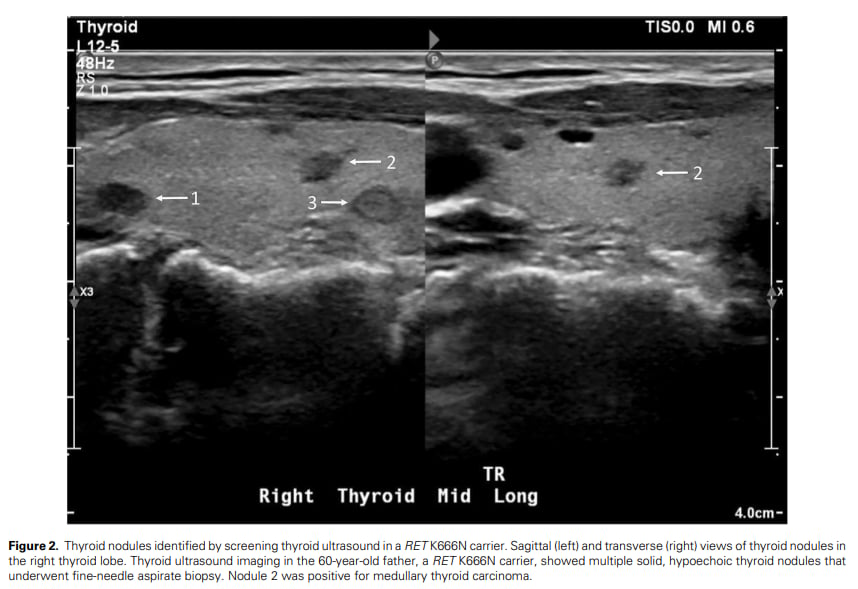

▲图2 RET K666N基因携带者通过甲状腺超声筛查发现甲状腺结节

细针穿刺活检(FNAB)的决策门槛

在普通人群中,细针穿刺活检(FNAB)通常有严格的尺寸阈值(例如,TI-RADS 4类结节需达到一定大小)。但对于像RET K666N携带者这样的甲状腺恶性肿瘤高风险个体,临床指南建议考虑在较低的尺寸阈值下进行FNAB。

本案例中,父亲的甲状腺超声显示3个亚厘米大小(小于常规FNAB阈值)的TI-RADS 4类结节。正是由于其RET胚系变异和轻度升高的降钙素,临床医生建议对可疑结节进行FNAB,最终确诊了MTC。这强调了在遗传性高风险人群中,临床判断和生化指标的重要性高于单纯的影像学尺寸标准。